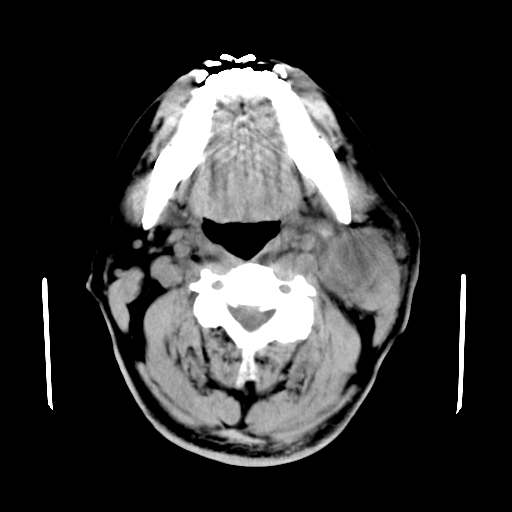

以下是引用卜一在2007-8-6 21:23:00的发言:[br]定位:左侧胸锁乳突肌内侧 颌下腺下后方。特征:弥漫性生长 软组织密度肿块,界限不清,内隐约见低密度坏死。考虑:神经源性肿瘤或血管源性肿瘤。

以下是引用wangzhanshuang在2007-8-6 21:08:00的发言:[br]腮腺混合瘤